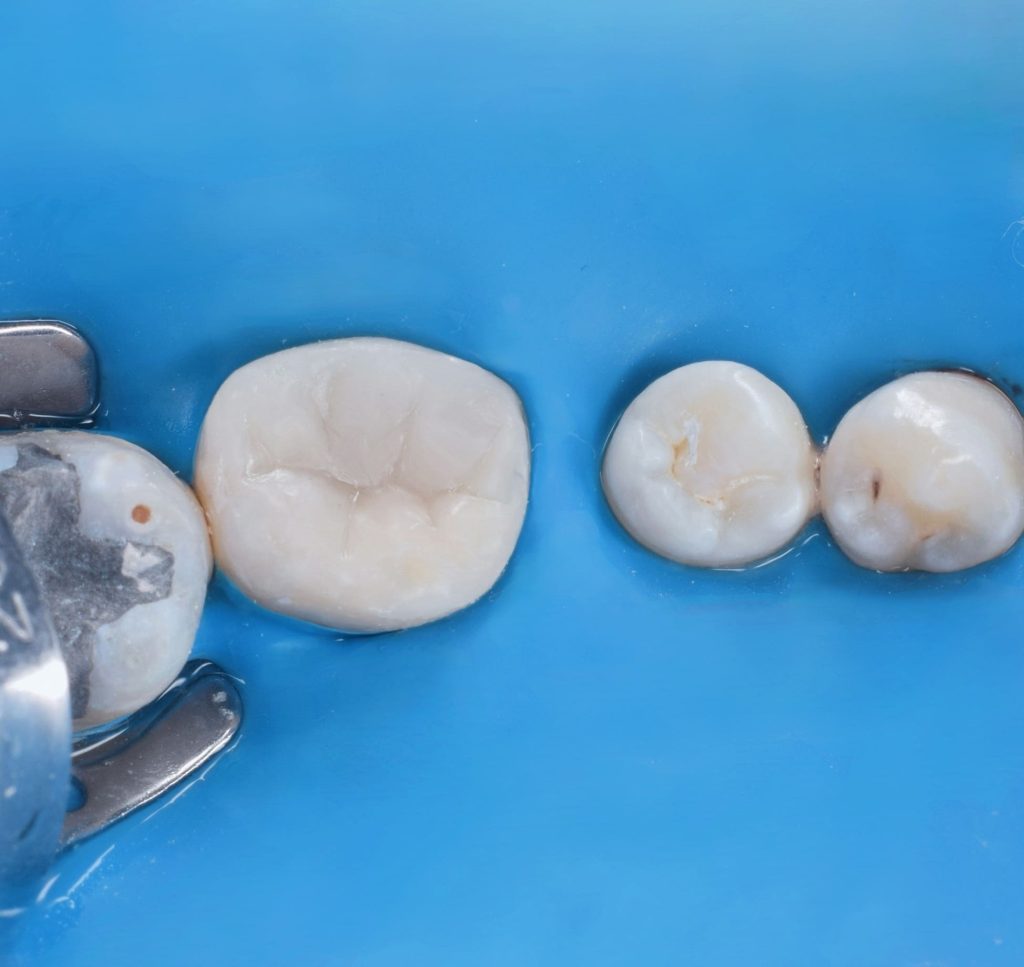

Direct photo after curing

Occlusal modeling - carving

Direct pic after polishing

Direct shot after polishing